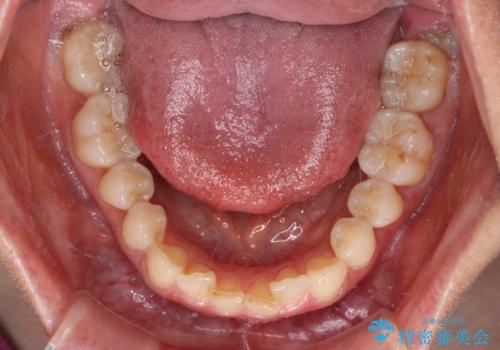

- 上下前歯のデコボコを気にして来院された患者様です。

叢生は軽度で、ワイヤー矯正でもマウスピース矯正でも対応可能な歯列でした。